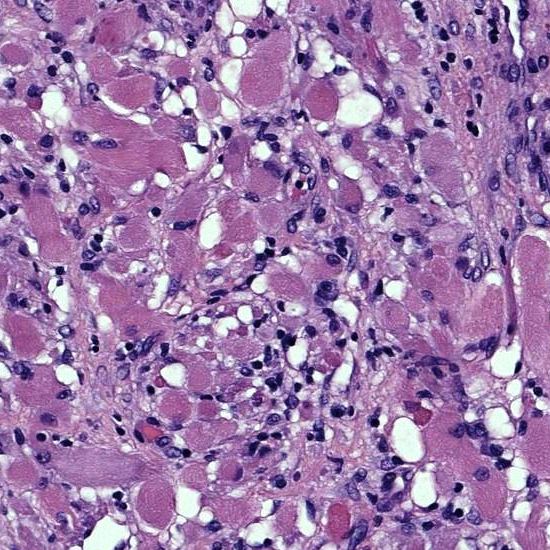

Rhabdomyomas are benign hamartomas of cardiac muscle.

Rhabdomyomas are the most common type of cardiac tumors in children.

Patients with tuberous sclerosis are at increased risk of rhabdomyomas.

Rhabdomyomas normally arises in the ventricle.